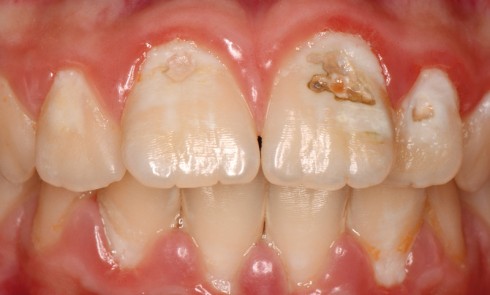

Article réservé à nos abonnés Carie précoce du jeune enfant

Malgré les progrès de prévention de la maladie carieuse, il est encore fréquent de recevoir en consultation d’odontologie pédiatrique de...